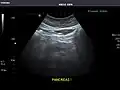

Pancreas: Visualized portions unremarkable.

Pancreas -